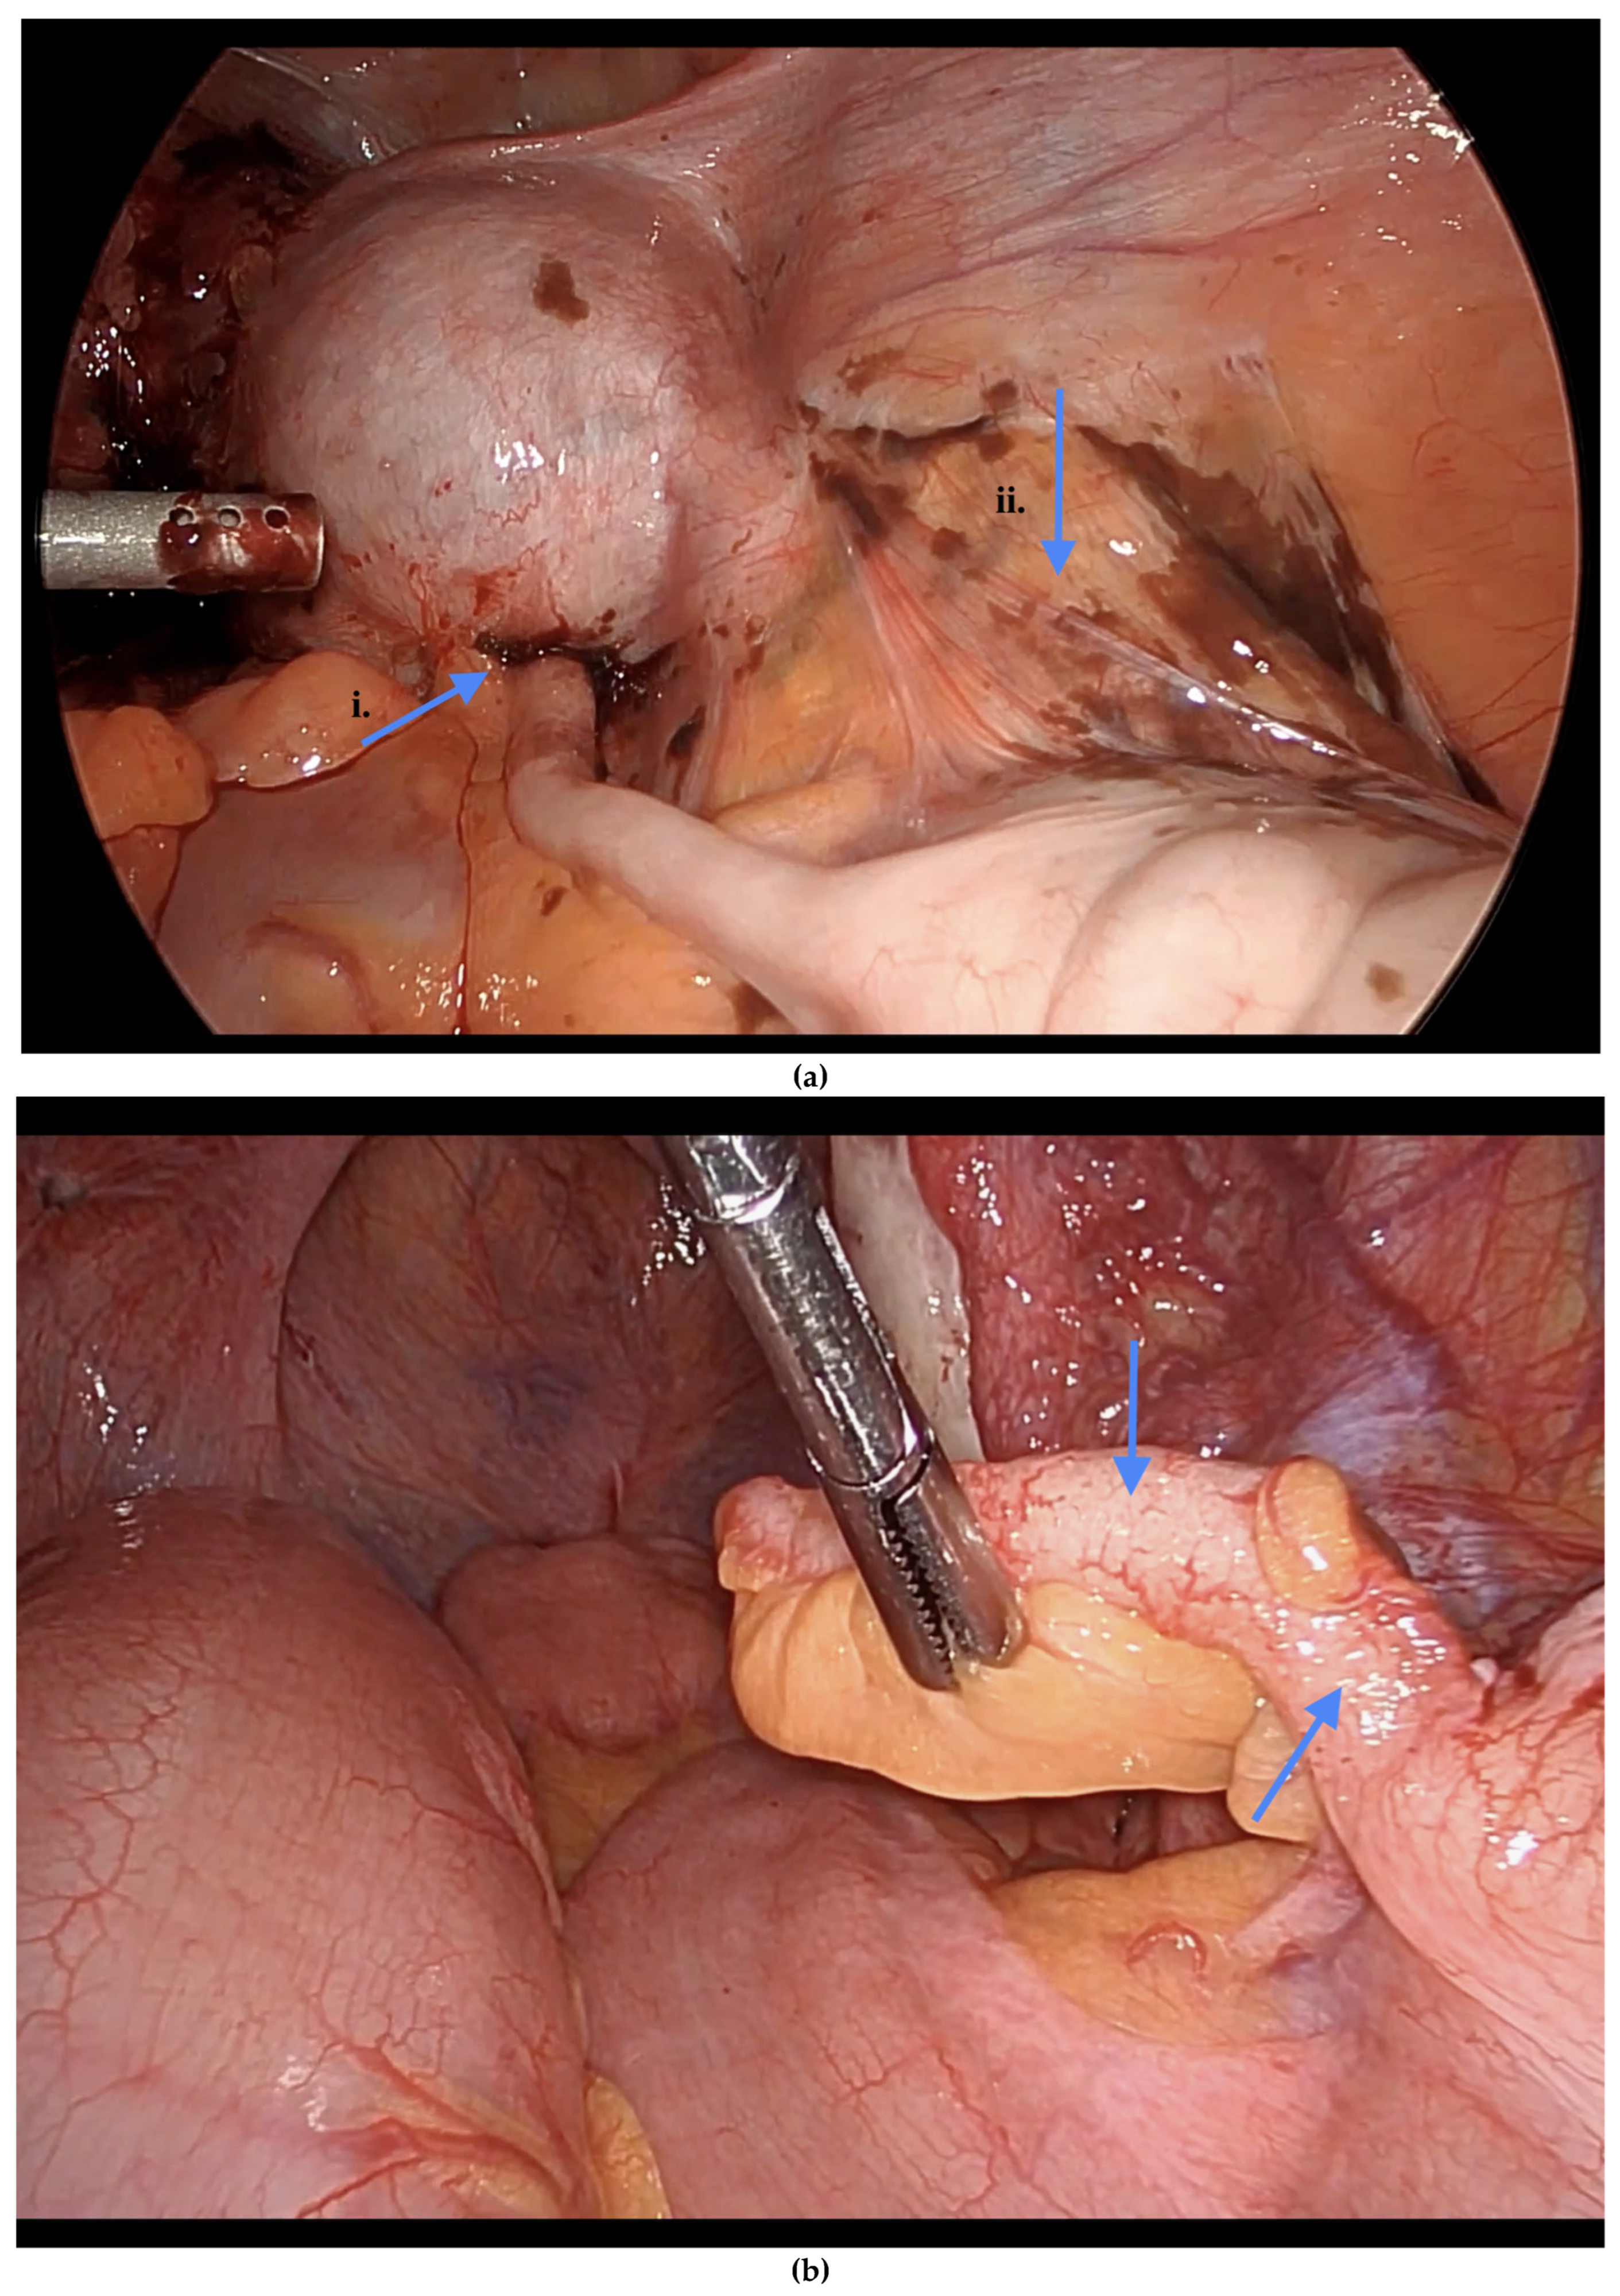

Figure 1. (a) Endometriosis on the appendix and mesoappendix. (b) Endometriosis nodule at the base of the appendix. Blue arrows indicate (a) endometriosis involving the appendix and mesoappendix, and (b) an endometriosis nodule at the base of the appendix.

Informed consent was obtained preoperatively, which included a discussion of the possibility of intraoperative appendectomy if appendiceal abnormalities were identified. During surgery, after optimal excision and ablation of endometriotic lesions, the appendix was carefully evaluated for evidence of endometriotic implants, serosal abnormalities, adhesions, fibrous obliteration, or features suggestive of acute or chronic appendicitis (Figure 1, Figure 2 and Figure 3). If abnormal findings were present, intravenous metronidazole was administered for infection prophylaxis, and a laparoscopic appendectomy was performed using the existing port sites [15]. The surgical technique included division of the mesoappendix, followed by transection and closure of the appendiceal base using a vascular stapler. The specimen was placed into a laparoscopic retrieval pouch and sent for histopathologic analysis [15,16].

Among the 216 patients with confirmed appendiceal abnormalities, many presented with more than one pathological finding (Figure 1, Figure 2 and Figure 3). Specifically, 34 patients (14.41%) had histologically confirmed appendiceal endometriosis lesions, 140 patients (59.32%) showed focal or serosal adhesions, 82 (34.75%) demonstrated fibrous obliteration, typically observed as obliteration of the appendiceal tip, and 20 (8.47%) exhibited signs of inflammation. Notably, three cases were diagnosed with neuroendocrine tumors of the appendix: one was confirmed to be malignant, while the other two were benign (Table 2).